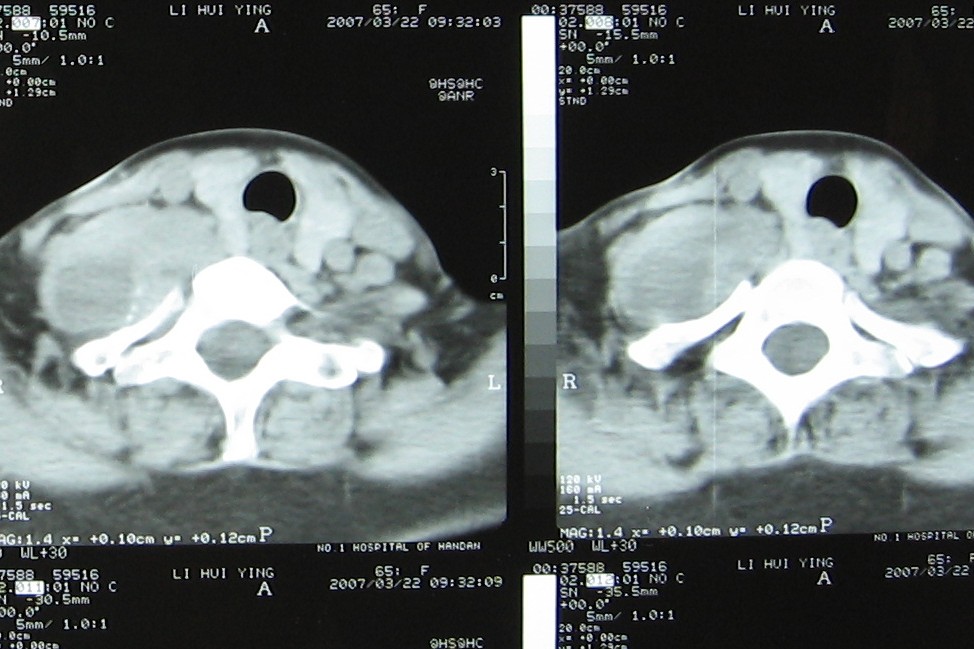

标题: CT7396:病人女65岁主因颈部肿疼伴上肢麻木4年近来加重入院 [打印本页]

标题: CT7396:病人女65岁主因颈部肿疼伴上肢麻木4年近来加重入院

支持考虑:神经原性肿瘤。(右侧椎间孔扩大,椎板破坏,局部明显的软组织肿块,并与椎管 神经根关系密切。)

支持考虑:神经源性肿瘤(右侧椎间孔扩大,椎板破坏,局部明显的软组织肿块,并与椎管神经根关系密切)。